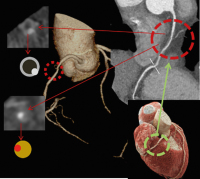

Abbildung 3: Diverse Plaques: Oberfl. stabile kalzifizierte Plaque in der proximalen LAD. (A): Längs-, (B): Querschnitt; (C): kleine, stabile, kalzifizierte Plaque in der proximalen RCA im Querschnitt (D), mehrere stabile kalzifizierte Plaques im LM oben und rechts unten im Längs-, links unten im Querschnitt in der Bifurkation; (E): Ausgeprägte Plaquelast in der LAD mit 50 HU einem Fibroatherom entsprechend; (F): Nicht-kalzifizierte Plaque in der RCA (F) im Längs- und (G) im Querschnitt (Fibroatherom); (H): Gemischte Plaque mit vorwiegend nicht-kalzifiziertem Fibroatherom und einem lipidreichen Anteil (30 HU), (I): im Querschnitt, kleiner Kalkspot um 14h, kleine Kalkschale 17–19h, zentral kleines Lumen, hohe Plaquelast im Halbkreis von 19–20h; (J): typisches NRS, hypodenser Plaque (51 HU) umgeben von einem hellen Ring, Lumen 15–17h; gemischte Plaque im Längsschnitt; (L): ca. 25 % Lumen, 50%ige Flächenstenose im distalen Hauptstammdrittel durch gemischte vulnerable Plaque mit positivem Remodelling, Kalkspot 20–22h, (M): 3D-Rekonstruktion der Hauptstammtrifurkation, siehe positives Remodelling im Winkel zwischen distalem LM und LAD. LM: Left Main; LAD: Left Anterior Descending Artery; RCA: Right Coronary Artery; NRS: Napkin Ring Sign; HU: Hounsfield Units